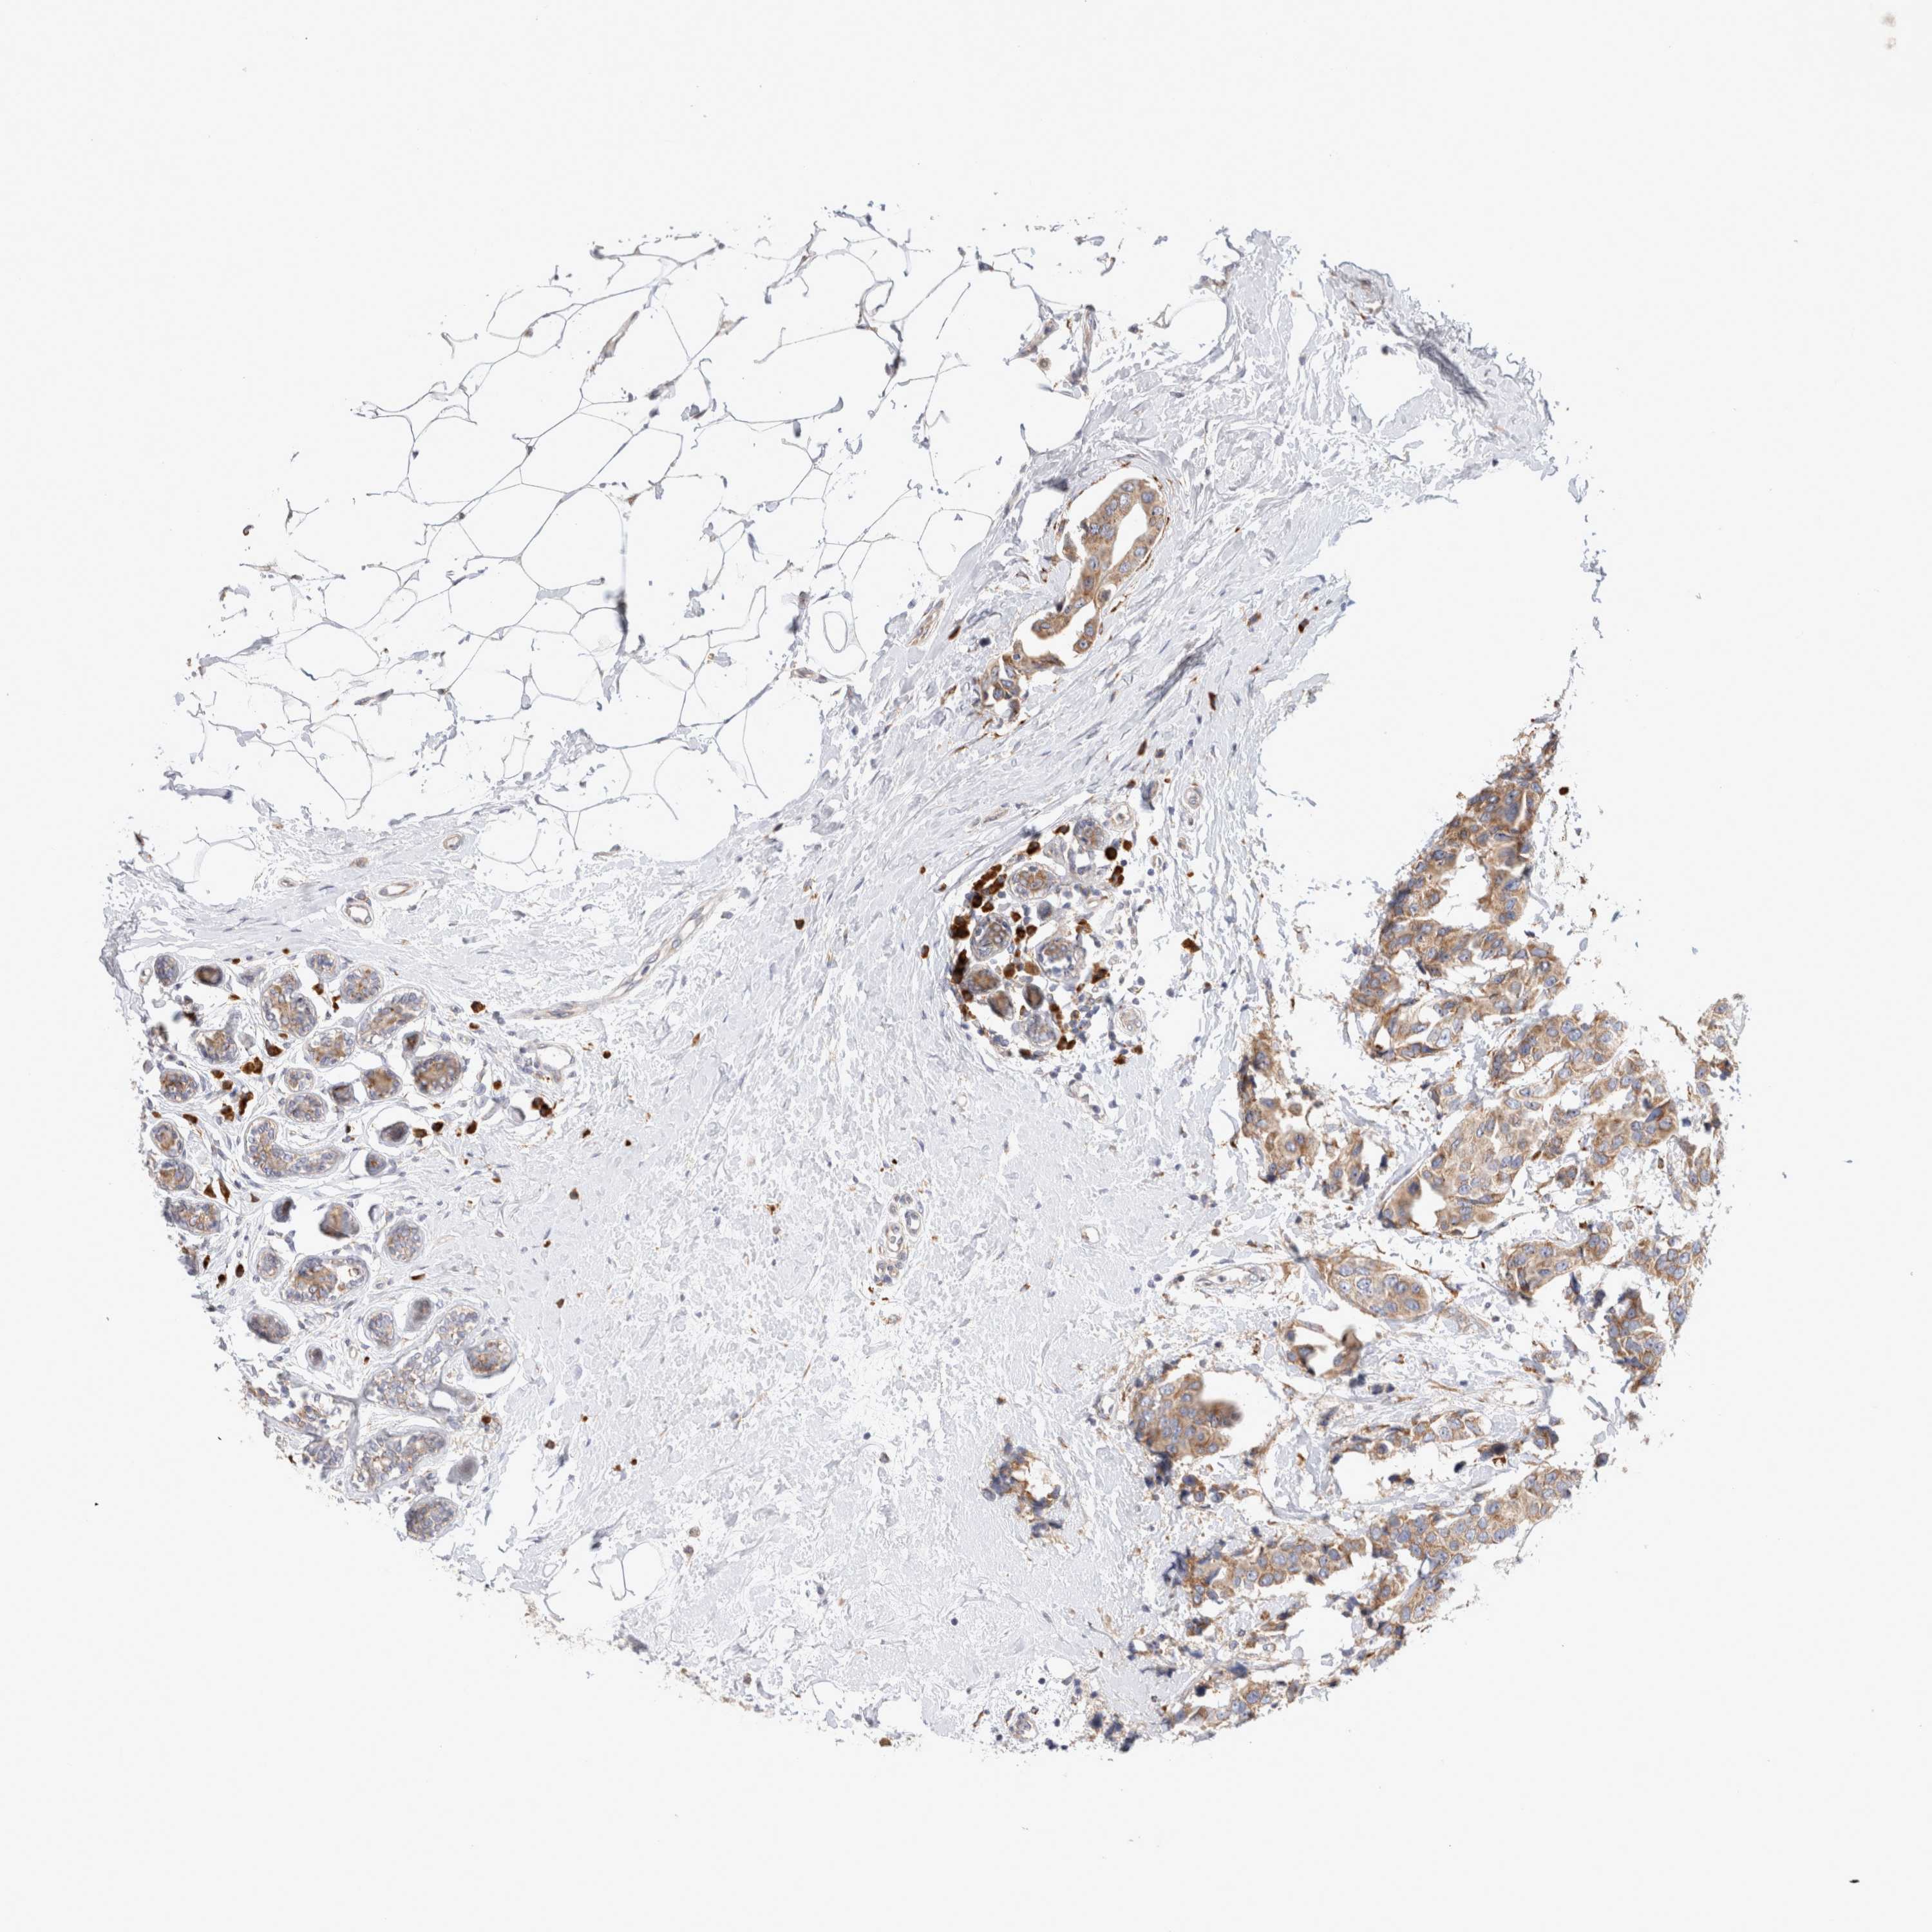

CANCER BREAST CANCER Show tissue menu

BRCA TCGA BRCA VALIDATION PROTEIN EXPRESSION

Breast cancer

Human cancer